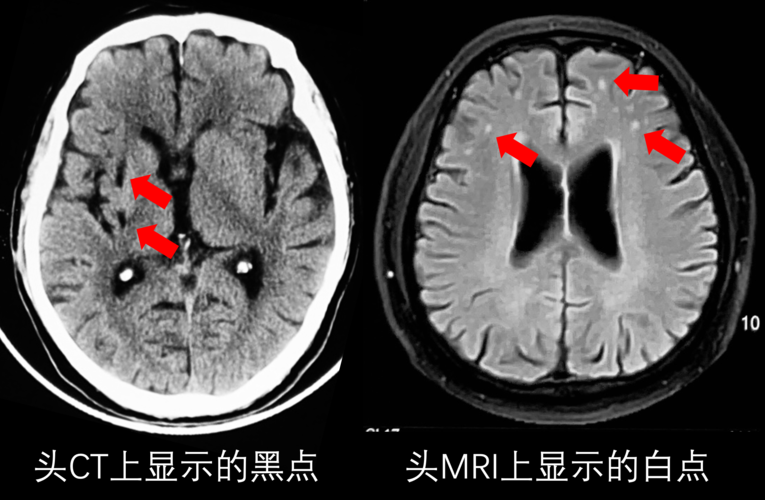

缺血灶是什么意思

缺血灶是什么病

缺血灶ct表现

脑缺血灶图片

脑缺血CT